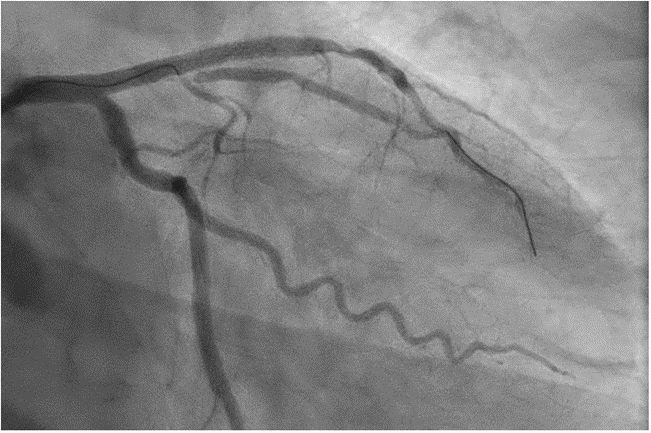

图2:撤出原侧支导丝后重新送入对角支导丝

再次PCI时首先使用3.0×20mm非顺应性球囊对LAD病变进行预扩张,随后植入1枚3.5×30mm药物洗脱支架。支架植入期间,于第一对角支保留1根导丝作为侧支保护导丝。支架释放后,撤出原侧支导丝,并重新送入对角支导丝,拟行侧支开口球囊扩张(图2)。